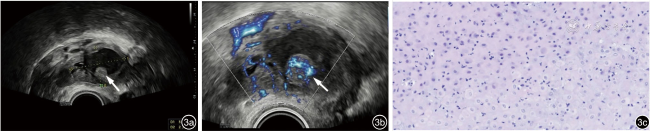

3.病例6:患者29岁,平素月经规律,痛经阳性,需口服止痛药缓解。此次停经42 d,未诉不适。超声检查提示宫内早孕,右侧卵巢见一多房囊性结构(图3a),大小约3.8 cm×2.9 cm×3.0 cm,内透声差,与周围组织粘连,子宫滑动征阴性,囊壁可见数枚乳头样突起,大者约1.2 cm×1.2 cm,CDFI示乳头内可见较丰富血流信号(图3b)。停经8+周行超声复查,双侧卵巢囊肿大小及乳头情况变化不明显,CDFI 示乳头内可见稍丰富血流信号。该患者实验室检查示CA125为65.9 U/ml(正常范围:<35 U/ml)。因可疑卵巢交界性肿瘤,于停经14+周行腹腔镜下右侧卵巢囊肿剥除术,术中可见右侧卵巢与子宫右后壁紧密粘连,卵巢表面、直肠表面及子宫后壁表面均可见多发乳头样结构,呈淡黄色,质软,分离粘连,取子宫后壁表面及卵巢表面病灶送快速冰冻病理,病理回报:送检组织间质蜕膜样变,遂行右侧卵巢囊肿剥除术,游离右侧卵巢,囊肿破裂,可见咖啡色黏稠液体流出,约50 ml,母胎均状态良好。病理诊断为子宫内膜异位囊肿,间质蜕膜样变(图3c)。术后恢复良好。

图3 停经42d,右侧附件肿块经阴道超声图像。图a为灰阶超声显示右侧卵巢一囊性为主的混合回声(箭头示囊内实性乳头状突起);图b为彩色多普勒超声显示囊内实性乳头状突起内可见少许血流信号(箭头示囊内实性乳头状突起处血流信号);图c为病理示卵巢子宫内膜异位囊肿并间质蜕膜化(HE ×200)